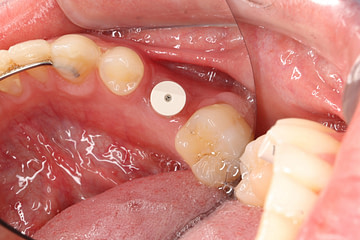

Master second-stage implant surgery techniques

Attendees will gain expertise in implant stability assessment, bone loss/integration management, digital workflows, and lab learning for optimal restoration design and communication.

This course offers invaluable hands-on experience through the use of live patient cases, allowing participants to apply their knowledge in a real-world clinical setting.

Explore advanced soft tissue management strategies

Delve into cutting-edge soft tissue management strategies, equipping participants with the skills to optimize aesthetic and functional results.

Select the perfect healing abutments

Learn to meticulously select the ideal healing abutments, ensuring a seamless transition to the final implant restoration.

Comprehensive implant integration assessment methods

This course provides comprehensive training in advanced assessment methods, enabling attendees to thoroughly evaluate implant integration and plan for successful restorations.

Unveiling the intricacies of implant restoration design

Unveil the intricate details of implant restoration design, empowering participants to create customized, high-quality solutions for their patients.